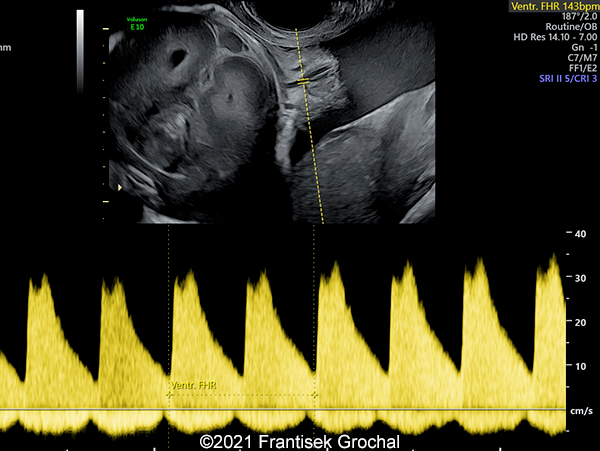

Case Report: A 24-year-old secundigravida, primipara presented to our office at 24 weeks and 6 days of her pregnancy due to a right-sided cranial parieto-occipital mass of the fetus. We obtained the following images.

Our ultrasound images at 24 weeks, 6 days show a highly vascularized, mostly solid mass measuring 58 x 45 x 34mm in the right-parieto-occipital subcutaneous region. Vascular supply of the lesion could be traced to the right vertebral artery. Repeat ultrasound exams done later in pregnancy demonstrated that the size of the mass remained stable with overall mass volume about 58 cm³.